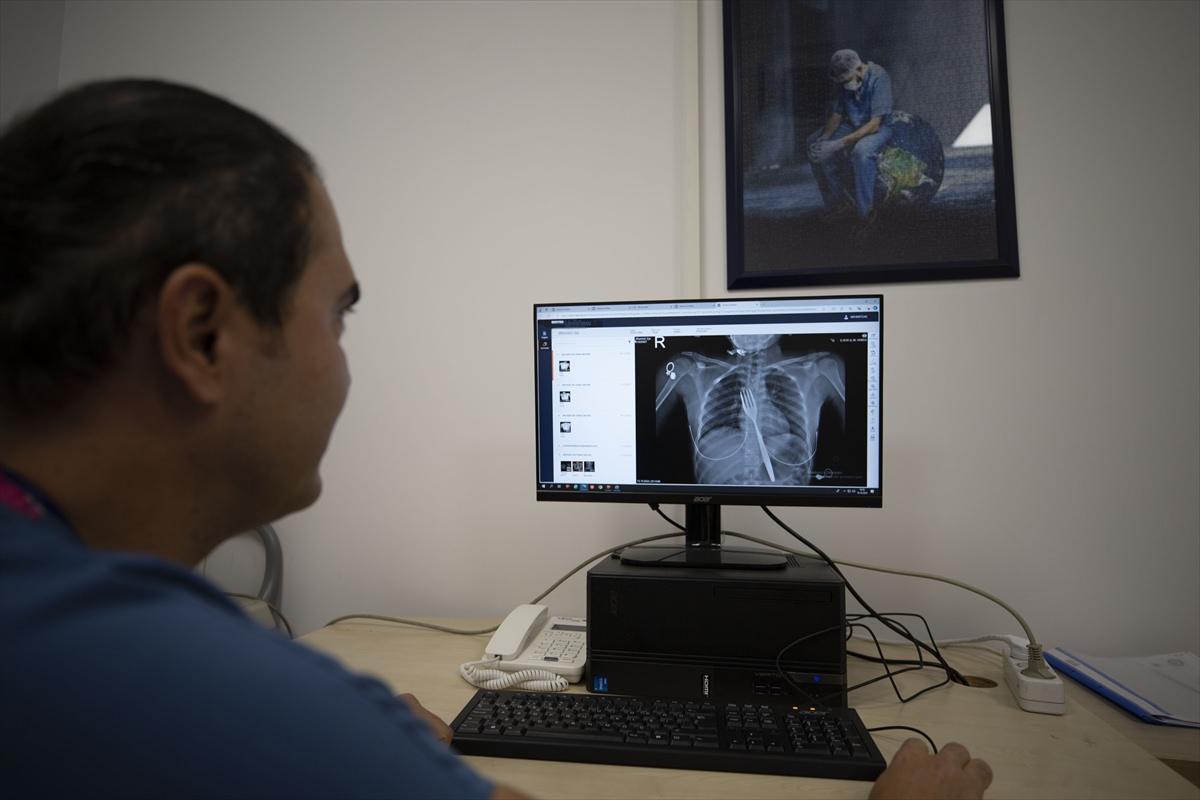

Vakayı ilk duyduğunda şaşırdığını anlatan Edizsoy, "Büyük bir çatalın tamamen yutulması şeklinde ortaya çıkan bu vakayı ilk duyduğumda doğru olmadığını düşündüm. Hasta 18 yaşında ve yabancı uyrukluydu. Türkçesi biraz zayıf olduğu için belki de yanlış anlaşılmalar olabileceğini düşündük. Ama hastanın filmini çektiğimizde gerçekten bir çatalın yemek borusunda olduğunu gördük." dedi.

Bu vakayı bilim dünyasına da sunacaklarına dikkati çeken Edizsoy, "Yabancı cisim yutulmasıyla ilgili birçok vaka var literatürde ama bunun gibi sıra dışı cisimler çok fazla yok. O yüzden biz bilimsel olarak da bunu diğer meslektaşlarımızla paylaşmayı düşünüyoruz. Bu konuda bir makale yazacağız. Bu kadar büyük bir cismin yutulması sıra dışı, böyle bir cisim yutulması ile karşılaşmamıştım." ifadesini kullandı.